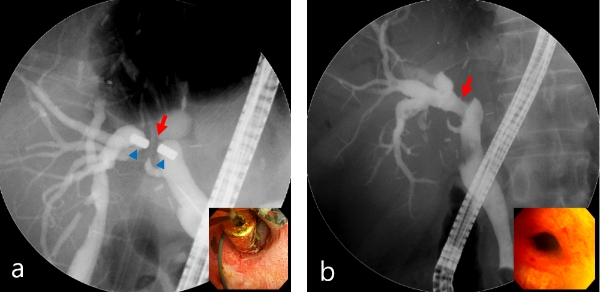

이미지 확대보기자기압축문합술은 담즙관 협착시 자석이 지나갈 통로를 확보한 뒤 자석을 문합부와 그 맞은편에 위치토록 조정해 자석 사이에 위치한 조직이 지속적인 압력을 받아 괴사하면서 떨어지도록 하는 시술이다.

한편 교수팀은 지난 2007년 국내 최초 자기압축문합술 도입 이후, 지난 2011년 간이식 후 발생한 문합부 완전폐쇄 환자 12명에게 자기압축문합술을 성공했다. 2015년 다양한 담관 수술 후 발생한 양성 담관 협착 환자에서 자석압축문합술을 시행해 총 5명의 환자에게서 막힌 담즙관이 다시 개통됐다는 연구논문을 발표했고 2017년에는 자기압축문합술을 시행 받은 39명 환자의 장기간 치료 결과 재협착 비율이 낮은 연구 결과를 발표했다.